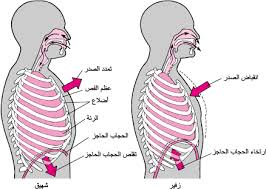

احد اجهزة الجسم له وظيفة حيوية ومهمة مكون من عدة اعضاء تعمل معا من ان تؤدي وظيفة جهاز التنفس وهي ادخال الاوكسجين الموجود في الهواء الى الدم بواسطة الشهيق واخراج ثاني اوكسيد الكربون من الم الى الخارج الجسم بواسطة الزفير

تَتَلَخَّصُ عَمَلِيَّة التّنَفُّسِ بِأَخْذِنا غازَ الأوكسجين مِنَ الْهَواءِ مُباشَرَةً (شَهيقٌ) لِضَخِّهِ في الدَّمِ، وتُخَلِّصُنا

من غازِ ثاني أُكْسيدِ الْكَرْبونِ (زَفيرٌ) الَّذي يَنْتُجُ في خَلايا الْجِسْمِ، وَالَّذي يُؤَدّي تَراكُمُهُ في الْجِسْمِ

الى ضرريُمْكِنُ أَنْ نُمَثِّلَ الْأوكْسُجينَ بِالْمادَّةِ الَّتي نَحْتاجُها لِطَبْخِ الطَّعامِ، بَيْنَما ثاني أُكْسيدِ الْكَرْبونِ

هو الرماد الْمُتَبَقّي بَعْدَ الطَّبْخِ، وَالَّذي لا حاجَةَ لَنا بِهِ

الحجاب الحاجز

الاضلاع